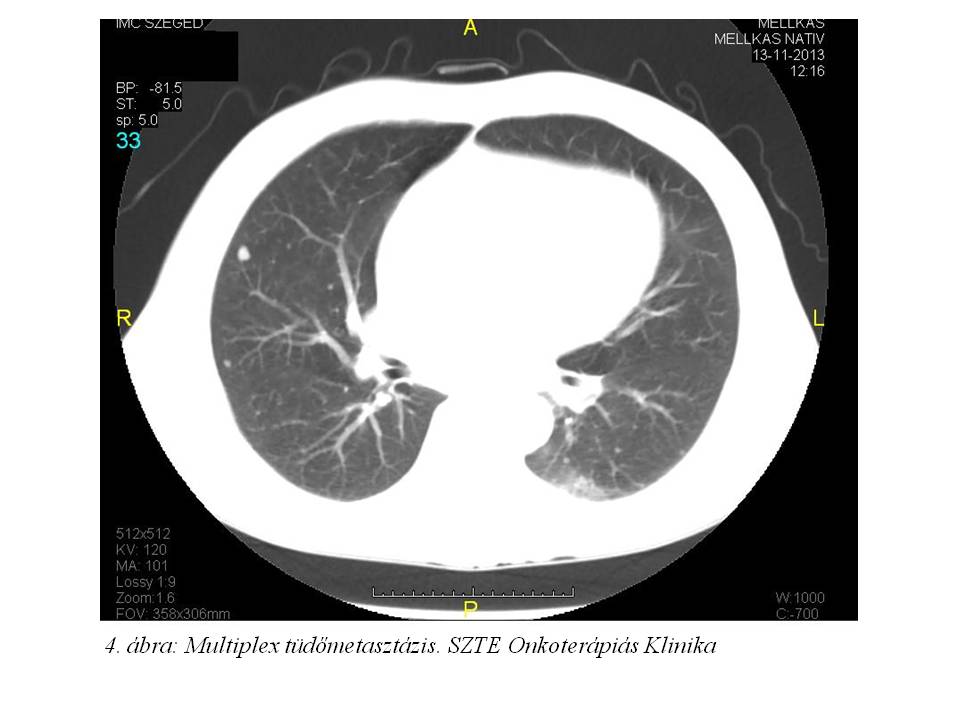

A has-kismedence CT vizsgálaton már felmerült tüdőmetasztázist az elvégzett mellkas CT vizsgálat (2013.11.13., 4. ábra) is megerősített: a tüdőben mindkét oldalon elszórtan néhány 3-6 mm nagyságú, lágyrész denzitású apró képlet ábrázolódik, mely metasisnak tartható.